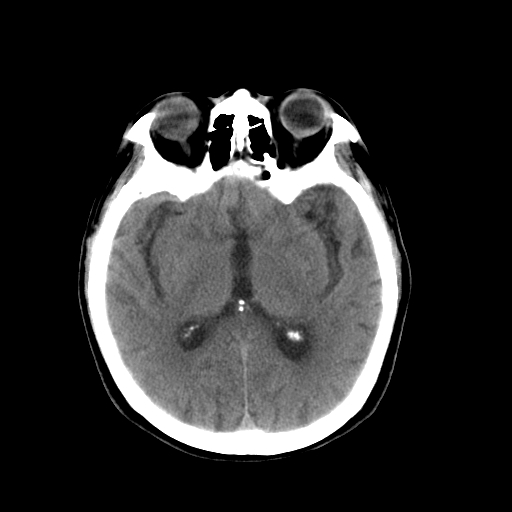

以下是引用dsl555在2008-11-11 18:52:00的发言:[br]四脑室后上方,四叠体池上方可见一小结节状稍高等密度影,比40天略大,建议mri或增强

以下是引用zjzjr在2008-11-12 8:28:00的发言:[br]四脑室后方略高密度影,周围环一低密度水肿带,四脑室受压变形,考虑小脑蚓部血肿吸收期或占位,建议增强